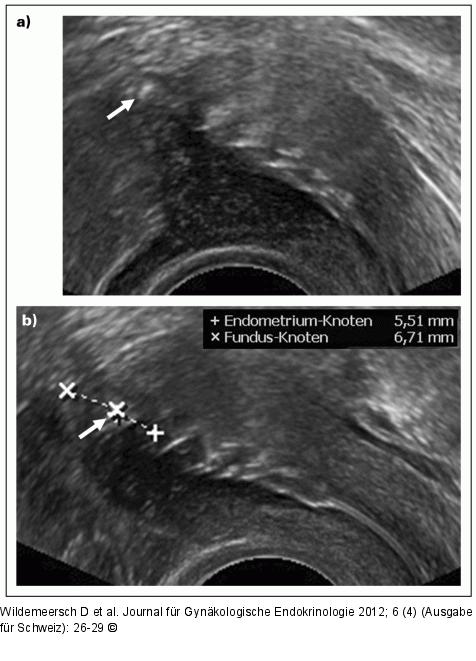

Abbildung 4a-b: Gynefix(R) - Verankerung (a) Dieses Ultraschallbild zeigt den Verankerungsknoten dicht an der Serosa, welche dadurch leicht vorgewölbt wird. Falls Zweifel an der korrekten Lage des Knotens bestehen, kann das IUD sofort entfernt werden und eine Wiedereinlage zu einem späteren Zeitpunkt erfolgen. Dies ist in diesem Fall geschehen; (b) Ultraschallbild derselben Patientin, einen Monat später. Der Verankerungsknoten ist in der Fundusmitte ca. 6 mm von der Serosa und vom Endometrium entfernt. |

(a) Dieses Ultraschallbild zeigt den Verankerungsknoten dicht an der Serosa, welche dadurch leicht vorgewölbt wird. Falls Zweifel an der korrekten Lage des Knotens bestehen, kann das IUD sofort entfernt werden und eine Wiedereinlage zu einem späteren Zeitpunkt erfolgen. Dies ist in diesem Fall geschehen; (b) Ultraschallbild derselben Patientin, einen Monat später. Der Verankerungsknoten ist in der Fundusmitte ca. 6 mm von der Serosa und vom Endometrium entfernt. |